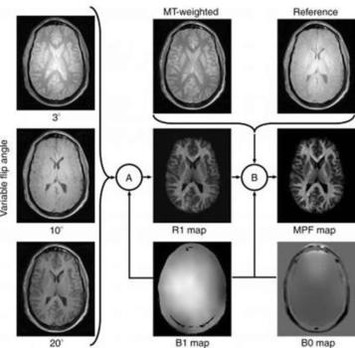

A new MRI study finds myelin loss in the gray matter of people's brains with MS is closely correlated with the severity of the disease.